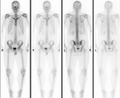

Normal bone scan in a person with osteopoikilosis